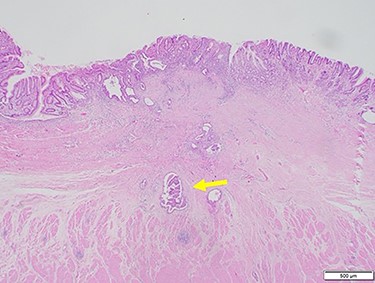

Chest and abdominal computed tomography (CT) showed no distant metastasis, but the tumor of the antrum was clearly visualized and was located close to the pancreatic head (Fig. 1). EGD revealed a large ulcerated lesion at the greater curvature of the antrum (Fig. 2). Hematoxylin and eosin staining of the biopsy specimen of the tumor confirmed a well-differentiated adenocarcinoma (tub1, tub2) (Fig. 3). The assessment of the HER2 expression by immunohistochemistry revealed the overexpression of HER2 (3+) in the biopsy tissue of the gastric tumor (Fig. 4).

Hematoxylin and eosin staining of the biopsy specimen of the tumor confirmed a well-differentiated adenocarcinoma (tub1, tub2).